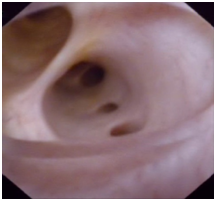

Figure 2 BC removal by choledochoscopy. The figure shows biliary mucosa swelling, erosion and ulceration, and the BC inside was caught by a stone basket.

BCs can prevent bile drainage, resulting in biliary obstruction and biliary tract infection. Percutaneous transhepatic cholangiography drainage is a common method for drainage of infected bile. After fistula extension, percutaneous transhepatic choledochoscopy can be implemented. We can observe the condition of the intrahepatic and extrahepatic bile ducts and remove multiple BCs with the help of choledochoscope, which is difficult by the conventional methods.19 In the process of removing BCs, we found that the BCs were shaped like the bile ducts, appearing as a hardened, dark material in the biliary ductal system with serious intrahepatic and extrahepatic bile duct injury. Some parts of the biliary mucosa showed patchy or strip defects, and mucosa ulcers were visible sometimes. After completely removing the BCs, the visualization of intrahepatic and extrahepatic bile ducts were improved, and patchy and bile duct mucosa were improved to varying degrees, showing reddish, smooth, rounded lumen and fresh bile secretion, and cholangiography displayed a very clear biliary tree (Figures 1–5).